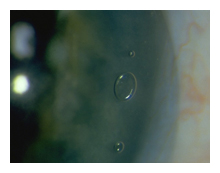

The ultimate release of the vitreous sometimes makes a large floater appear,

usually in the shape of a ring ("Weiss ring").